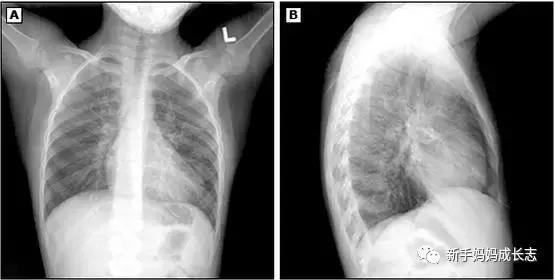

诊断依据(课本上的):发热,咳嗽,气促,肺部固定中小水泡音,X线-双肺下野中内带斑片状阴影。

一般都要有上述的症状(程度或轻或重),肺部听诊主要有大夫来完成(一般如果查体能听到固定中小水泡音就可以确诊肺炎)。有时需要胸部X射线来确定并确定肺炎累及的程度。

第一:影像相关

1、对于一般状况良好且可以在门诊治疗的疑似社区获得性肺炎的患儿,无需常规行胸片检查

2、对于初始抗菌药物治疗失败,需要验证是否存在肺炎并发症或病情加重的患儿应及时做胸片检查

3、胸部CT扫描和胸部侧位片不宜列为常规

4、在除外肺不张、肺梗死、肺出血等之后,胸片有实变的表现可诊断肺炎

5、胸片征象对肺炎的病原学的提示性差

6、对于临床上肺炎已康复,一般状况良好的患儿,无需反复胸片复查

上述是指南的标准,不过目前如果怀疑肺炎的孩子门诊还是都会拍胸片的。

6.胸片等影像学资料证实双侧或多肺叶受累或肺叶实变并肺不张、胸腔积液或短期内病变进展者